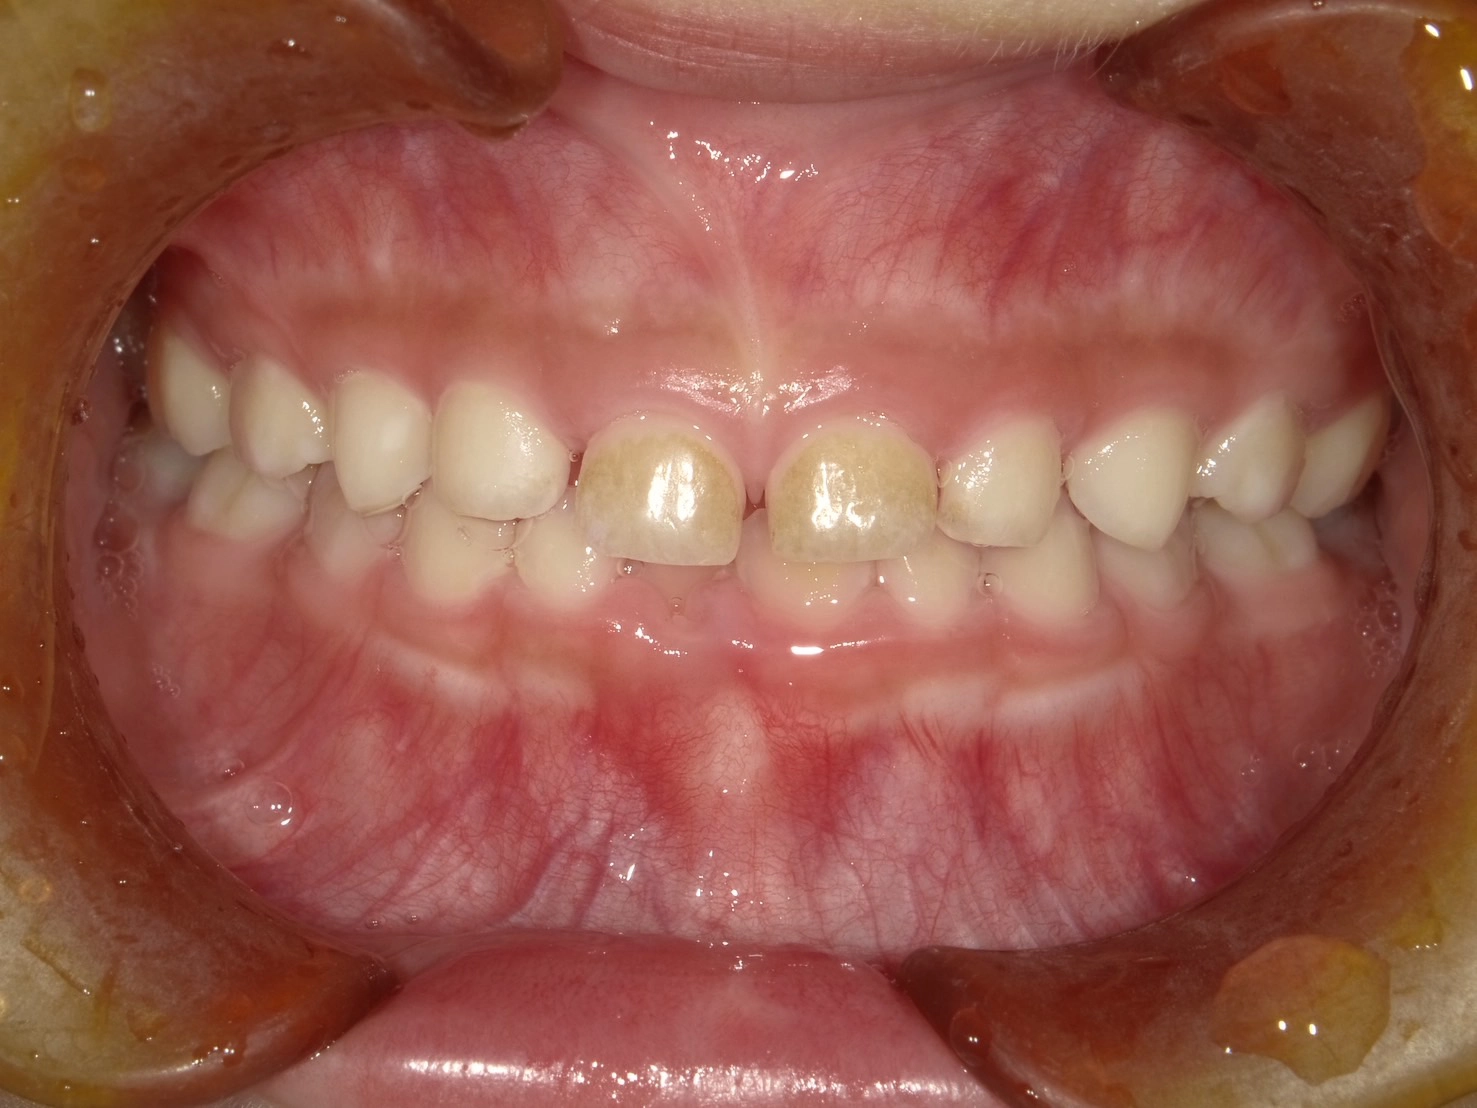

実際に小野歯科医院で行っているマイオブレースを用いた小児矯正の症例を紹介します。

どんどんきれいな歯並びになっていく様子を一緒に確認していきましょう!

治療前

術名 | マイオブレース矯正 |

---|---|

年齢 | 6歳 |

性別 | 男性 |

主訴 | 下の前歯のガタつきが気になる |

診断名 | 叢生 |

治療内容 | マイオブレース矯正 |

治療期間 | 治療開始2ヶ月時点での変化 |

費用 | 基本料33万(検査診断料.月々の調整料別途) |

リスク・副作用 | 特になし |